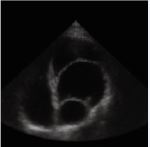

A 49-year-old male presented with complaints of intermittent palpitations for three years, increasing on exertion and associated with sweating. Clinical evaluation revealed atrial fibrillation with a controlled ventricular rate. Baseline echocardiography demonstrated a large mass in the interatrial septum measuring approximately 5.2 × 3.0 cm, suggestive of a cystic lesion with internal septations. Transesophageal Echocardiography (TEE) confirmed a large mass arising near the non-coronary sinus of Valsalva, raising suspicion of aneurysm with internal thrombus. Coronary angiography showed mild coronary artery disease. Cardiac MRI demonstrated an aneurysmal dilatation of the non-coronary cusp of the aortic sinus measuring 4.3 × 3.1 cm with eccentric mural thrombus, causing compression on the left atrium. No myocardial edema, perfusion defect, or late gadolinium enhancement was noted. CT coronary angiography further delineated a saccular aneurysm from the non-coronary sinus measuring 3.8 × 3.8 × 5.6 cm with non-enhancing thrombus, indenting the left atrium and right pulmonary vein. Calcified plaques causing mild luminal narrowing were noted in the left main coronary artery and left anterior descending artery. The total calcium score was 420. The cardiothoracic surgeon had assessed the operative risk to be significantly high in view of the patient’s very low body weight (40 kg), raising concerns regarding perioperative morbidity, hemodynamic instability, and postoperative recovery. These factors were clearly explained, and although surgery was advised, the patient declined the procedure after understanding the associated risks. In view of the high surgical risk and the patient’s informed refusal, we adopted a conservative management strategy. The patient was managed with rate control for atrial fibrillation and remains stable on follow-up (Figures 1-3).

Figure 2 CT Coronary Angiogram depicting saccular aneurysm from non-coronary sinus compressing left atrium and right pulmonary vein with peripheral thrombus.